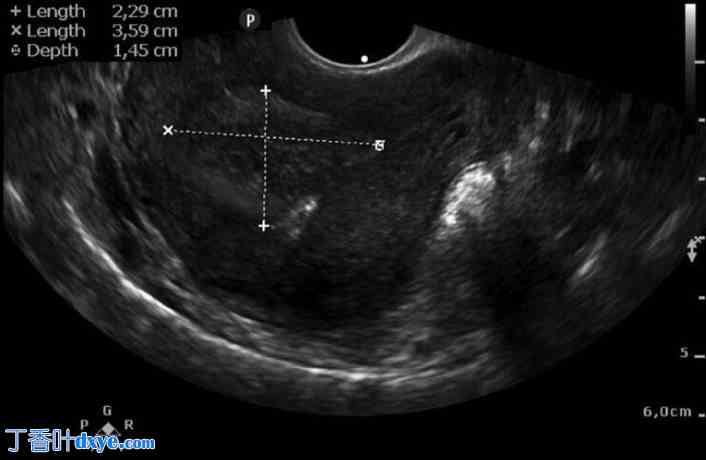

尽管持续使用炔雌醇/左炔诺孕酮50微克/125微克,但月经量仍未减轻。经阴道超声检查发现三个子宫肌瘤,包括一个位于子宫后壁、大小为36×37×40毫米的FIGO 2型子宫肌瘤(图1),以及两个分别位于前壁和后壁、大小为11×19×21毫米和27×33×30毫米的FIGO 5型子宫肌瘤。

图1. 经阴道超声检查显示治疗前的FIGO 2型子宫肌瘤。